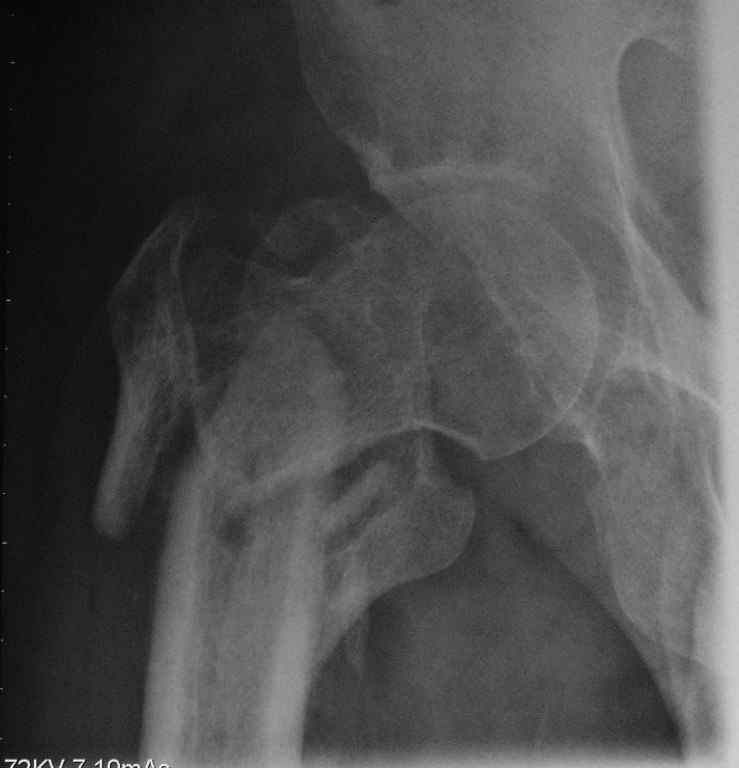

Пациент сорока лет с псевдартрозом правого бедра - исход оскольчатого чрезвертельного перелома с отрывом большого и малого вертелов. Поступил через 8 месяцев после травмы. По месту жительства лечили следующим образом: 2 месяца скелетное вытяжение, затем 2 месяца в кокситной повязке. После снятия гипса дали нагрузку. В настоящий момент имеется укорочение 6 см. Патологическая подвижность. По данным КТ - сращения нет, имеется аваскулярный некроз головки 2 стадии. В данном случае показано эндопротезирование тазобедренного сустава. Просим уважаемых коллег ответить на вопросы, которые возникли у нас по этому больному: 1. Имеет ли смысл выполнять первым этапом остеосинтез псевдартроза, учитывая, что нагрузка на сустав при наличии АНГБ противопоказана? 2. Возможно ли технически сразу выполнить эндопротезирование при наличии такого псевдартроза?

Вопрос в другом. 1) этот снимок не выглядит , как укорочение на 6 см. не понимаю

Форма головки сохранена, перелом, так скажем. не самый угрожающий в отношении ее "фатального" некроза.

>По данным КТ - сращения нет, имеется аваскулярный некроз головки 2 стадии

Известно, что травматическая этиология в образовании Аваскулярного Некроза головки играет важную роль, но при чрезвертельных переломах трудно представить повреждение MCA, обеспечивающей около 80% кровоснабжения головки бедра.

Если имеются данные изотопного сканирования, кстати при начальных этапах это не всегда дает 100% результат, можно было бы выставить. А то на рентгенограмме не видно явлений, указывающих на АВН.

Лучше сделать МРТ, которая поможет аккуратно определить все стадии АВН.

Исследования убедят в правильности принятия решения, и у 40 летнего идти на ревизионный протез считаю немного агрессивным.